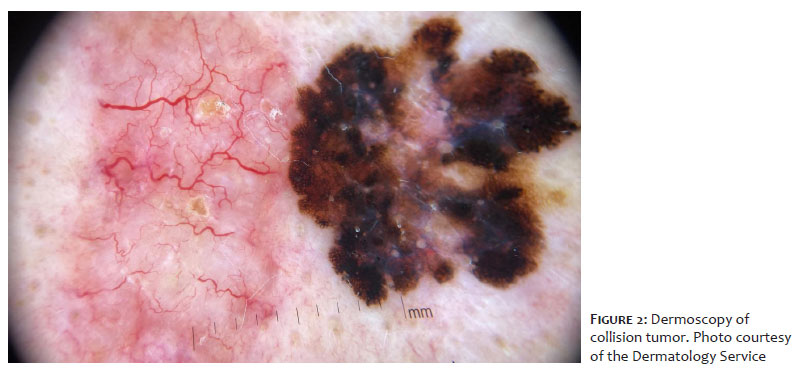

Complete dermatological examination revealed an asymmetric plaque with irregular borders measuring approximately 2.94 × 2.55 cm, consisting of two adjacent lesions with distinct characteristics (Figure 1). On the left, the lesion was erythematous, poorly defined, elevated, with coarse arborizing telangiectasias and small ulcerations on dermoscopy, measuring approximately 1.41 × 2.55 cm. On the right, the lesion was darkly pigmented, well-defined, measuring 1.57 × 1.53 cm, with a multicomponent dermoscopic pattern, showing an atypical network, branched streaks, amorphous areas, and a blue-gray veil (Figure 2). No lymphadenopathy was identified on physical examination.